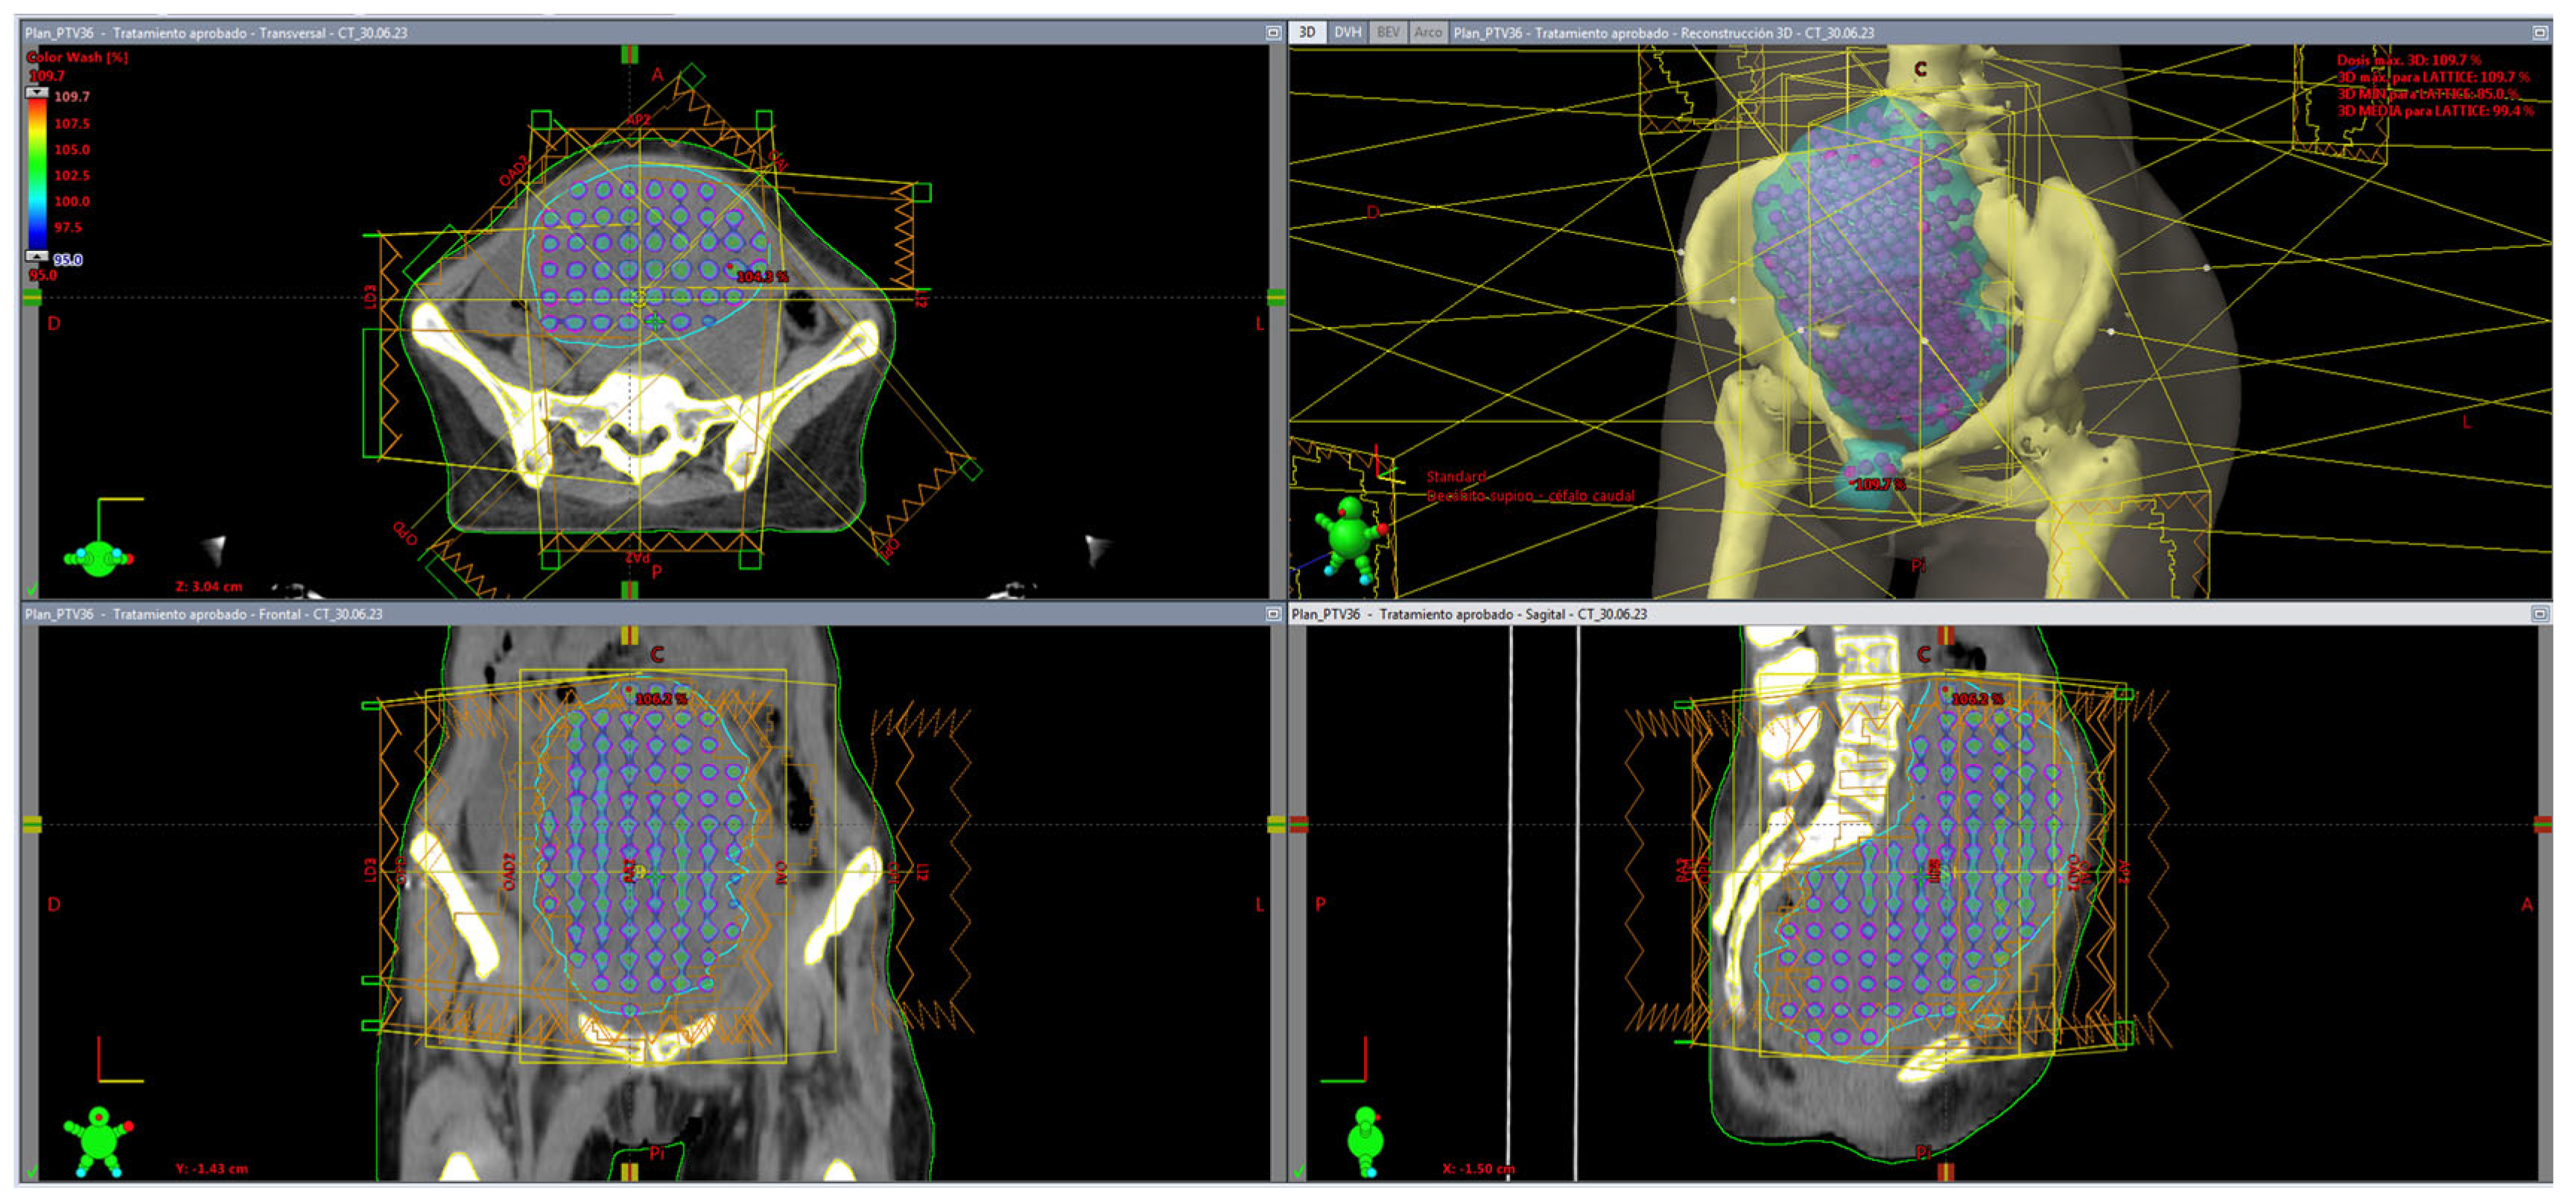

Automated Clinical Dosimetry Planning of Dense Lattice Radiation Therapy

2. Materials and Methods

3. Results